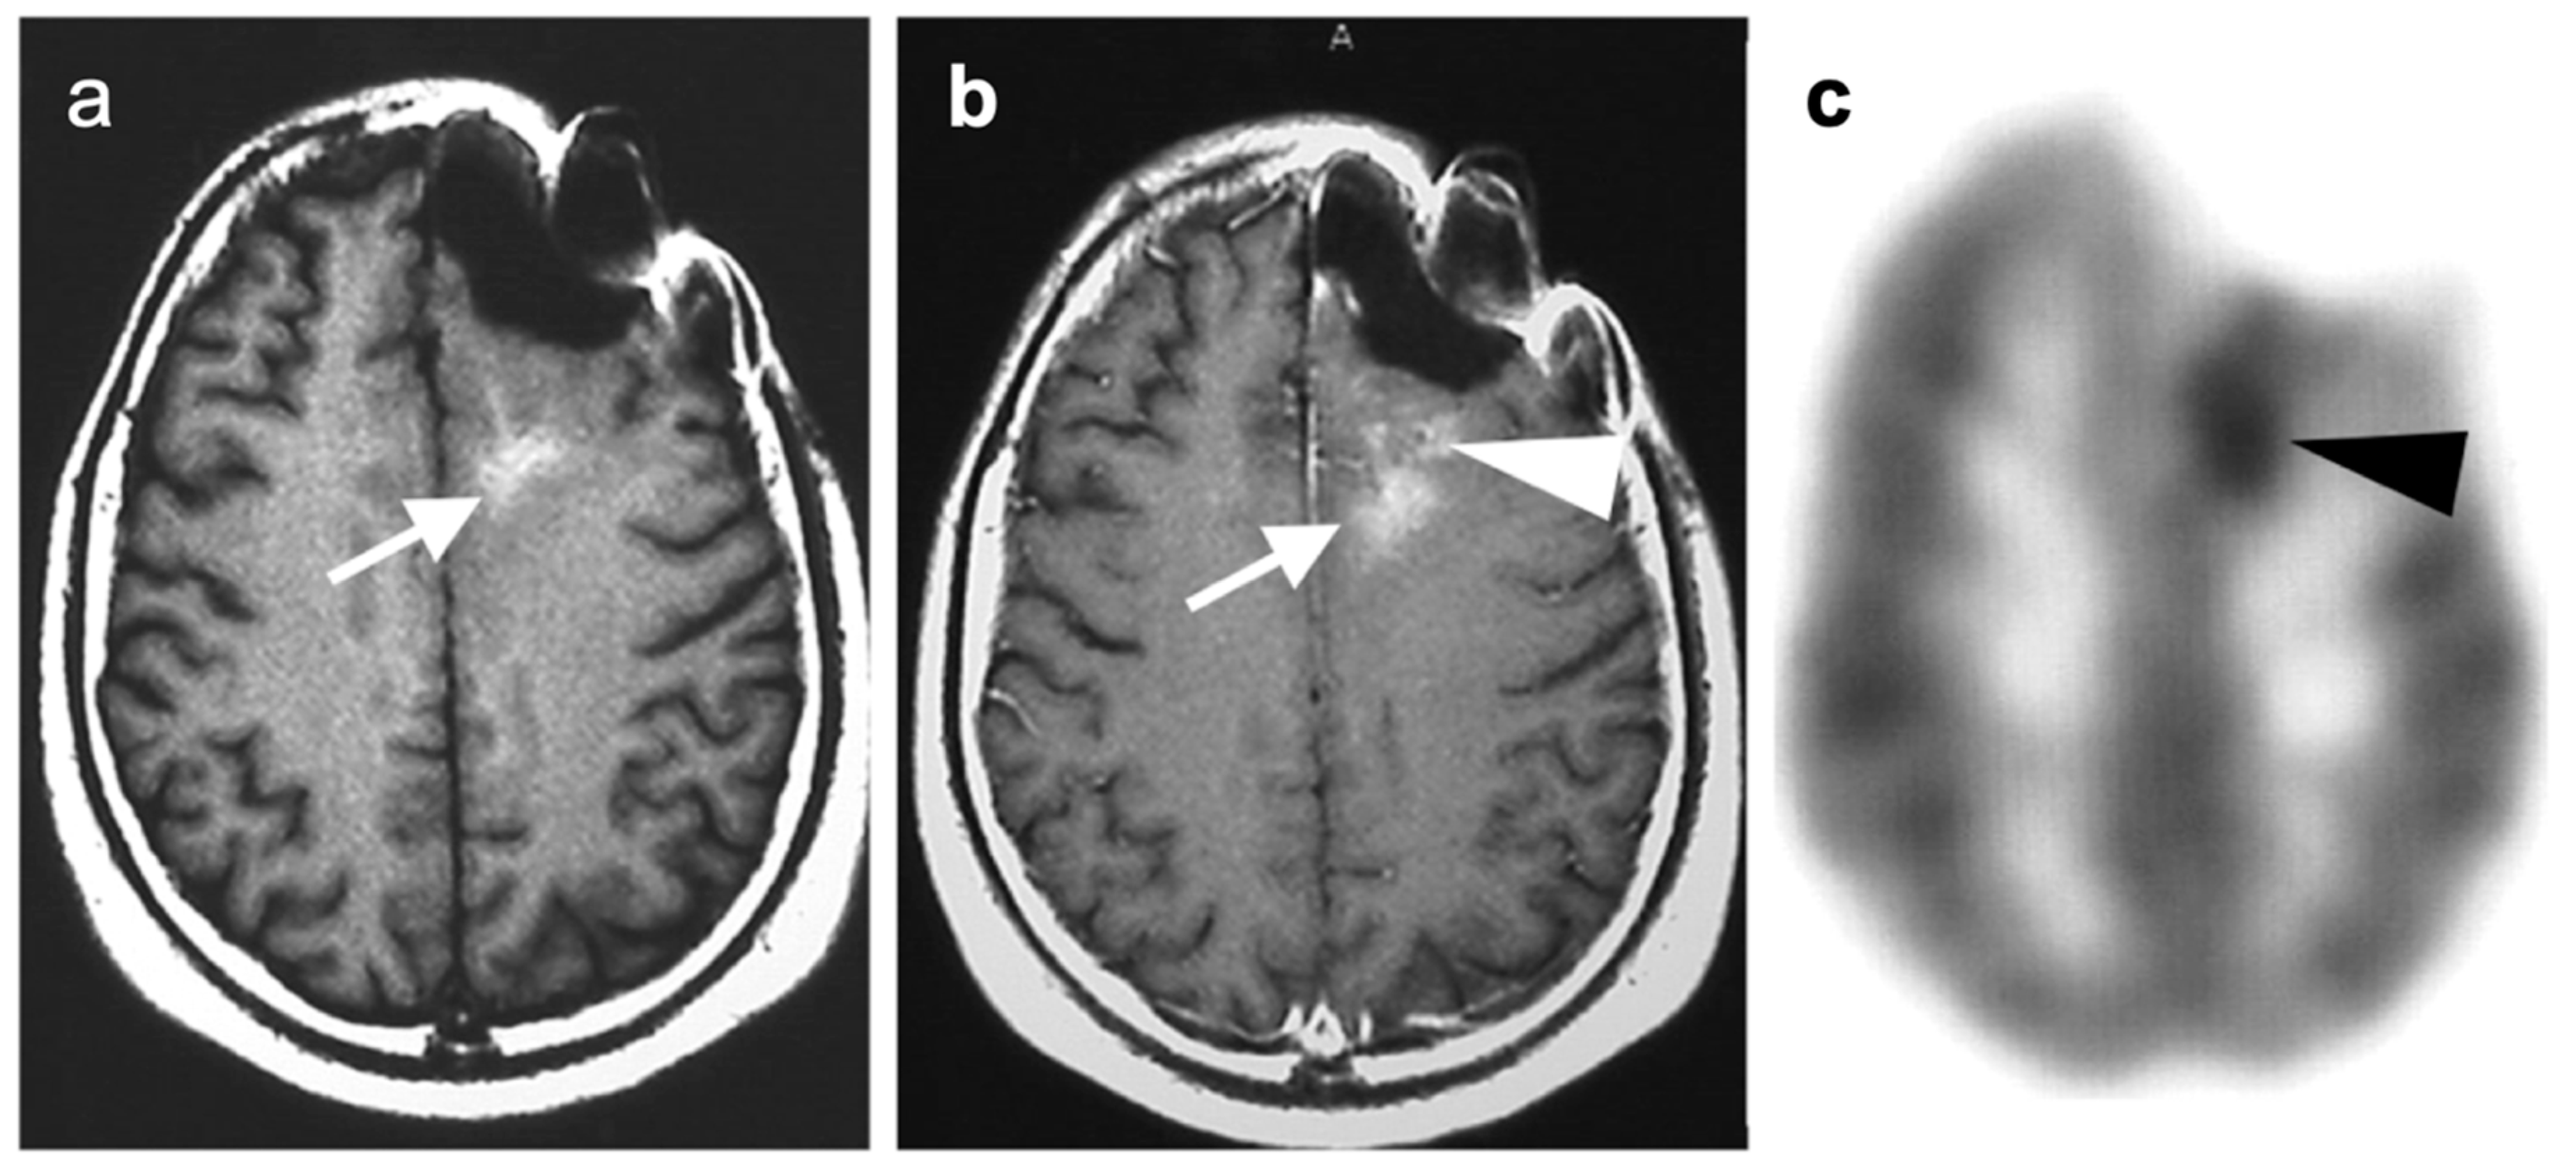

3.5. Brain Metastases

3.6. Response to Therapy

3.7. Meningioma